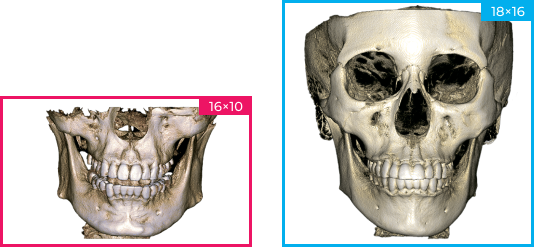

FOV 18×16

Свободные настройки FOV

Ортодонтия и ортогнатическая хирургия, анализ пазух носа и дыхательных путей, имплантология, двойной анализ ВНЧС, эндодонтия.

FOV 4x5 FOV 10x10 FOV 18x16

Изображения с высоким разрешением для точной диагностики

Получите исключительную чёткость изображения и настраиваемый объём сканирования с помощью RAYSCAN. Адаптируйте свои снимки в соответствии с вашими конкретными клиническими потребностями, и будьте уверены в том, что запечатлеете каждую сложную деталь и раскроете безграничные возможности.

FOV 18×16 см, 300 μm

FOV 10×10 см, 160 μm

FOV 4×5 см, 70 μm